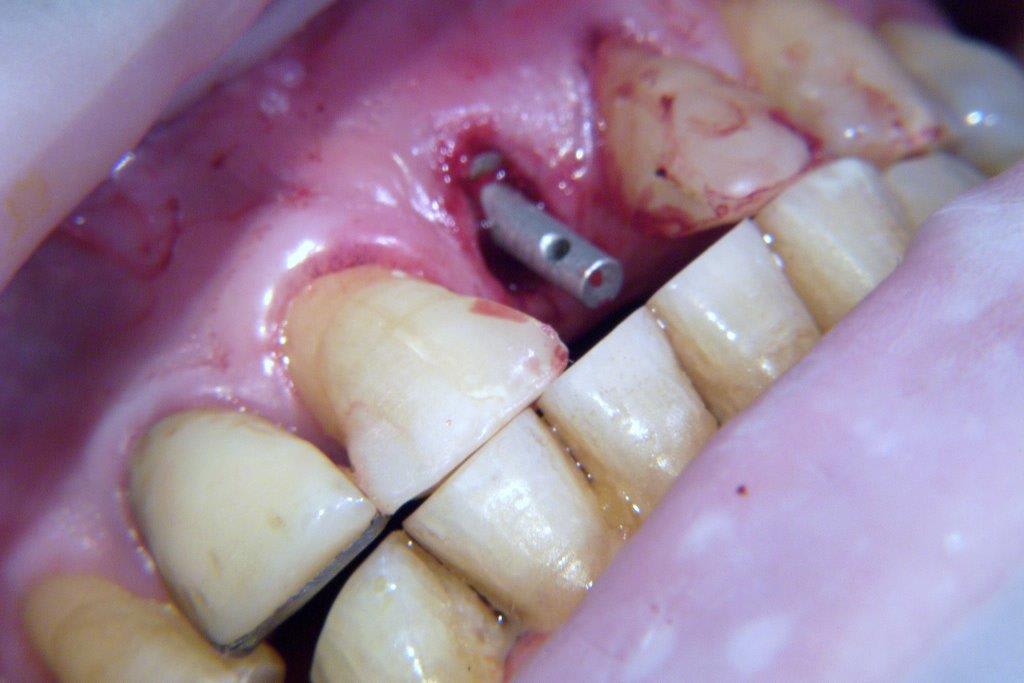

pour ceux que ça intéressent, une petite utilisation d'expansion de la paroi palatine, sur une avulsion d’incisive(racine fendue). toutes mes excuses pour la mauvaise qualité des photos.

Et à ton avis pourquoi ton incisive s'est fendue ? Y a qu'à regarder ta photo ...

Et donc tu mets un Implant dans ce contexte là .... faudra pas se demander pourquoi il y aura des complications prothétiques de type fracture de vis